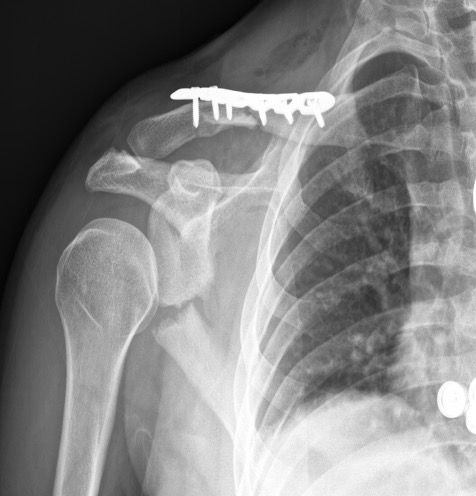

ORIF glenoid and clavicle

Displaced scapular neck

Glenoid fracture + lateral clavicle fracture + acromial fracture